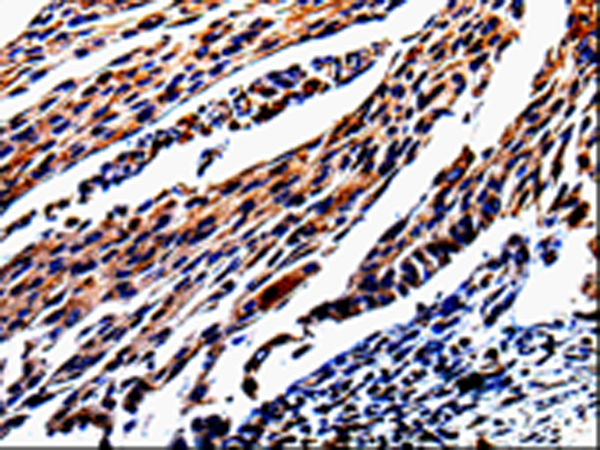

IHC positive control: |

Human cervical cancer and human lung cancer |

IHC Recommend dilution: |

25-50 |